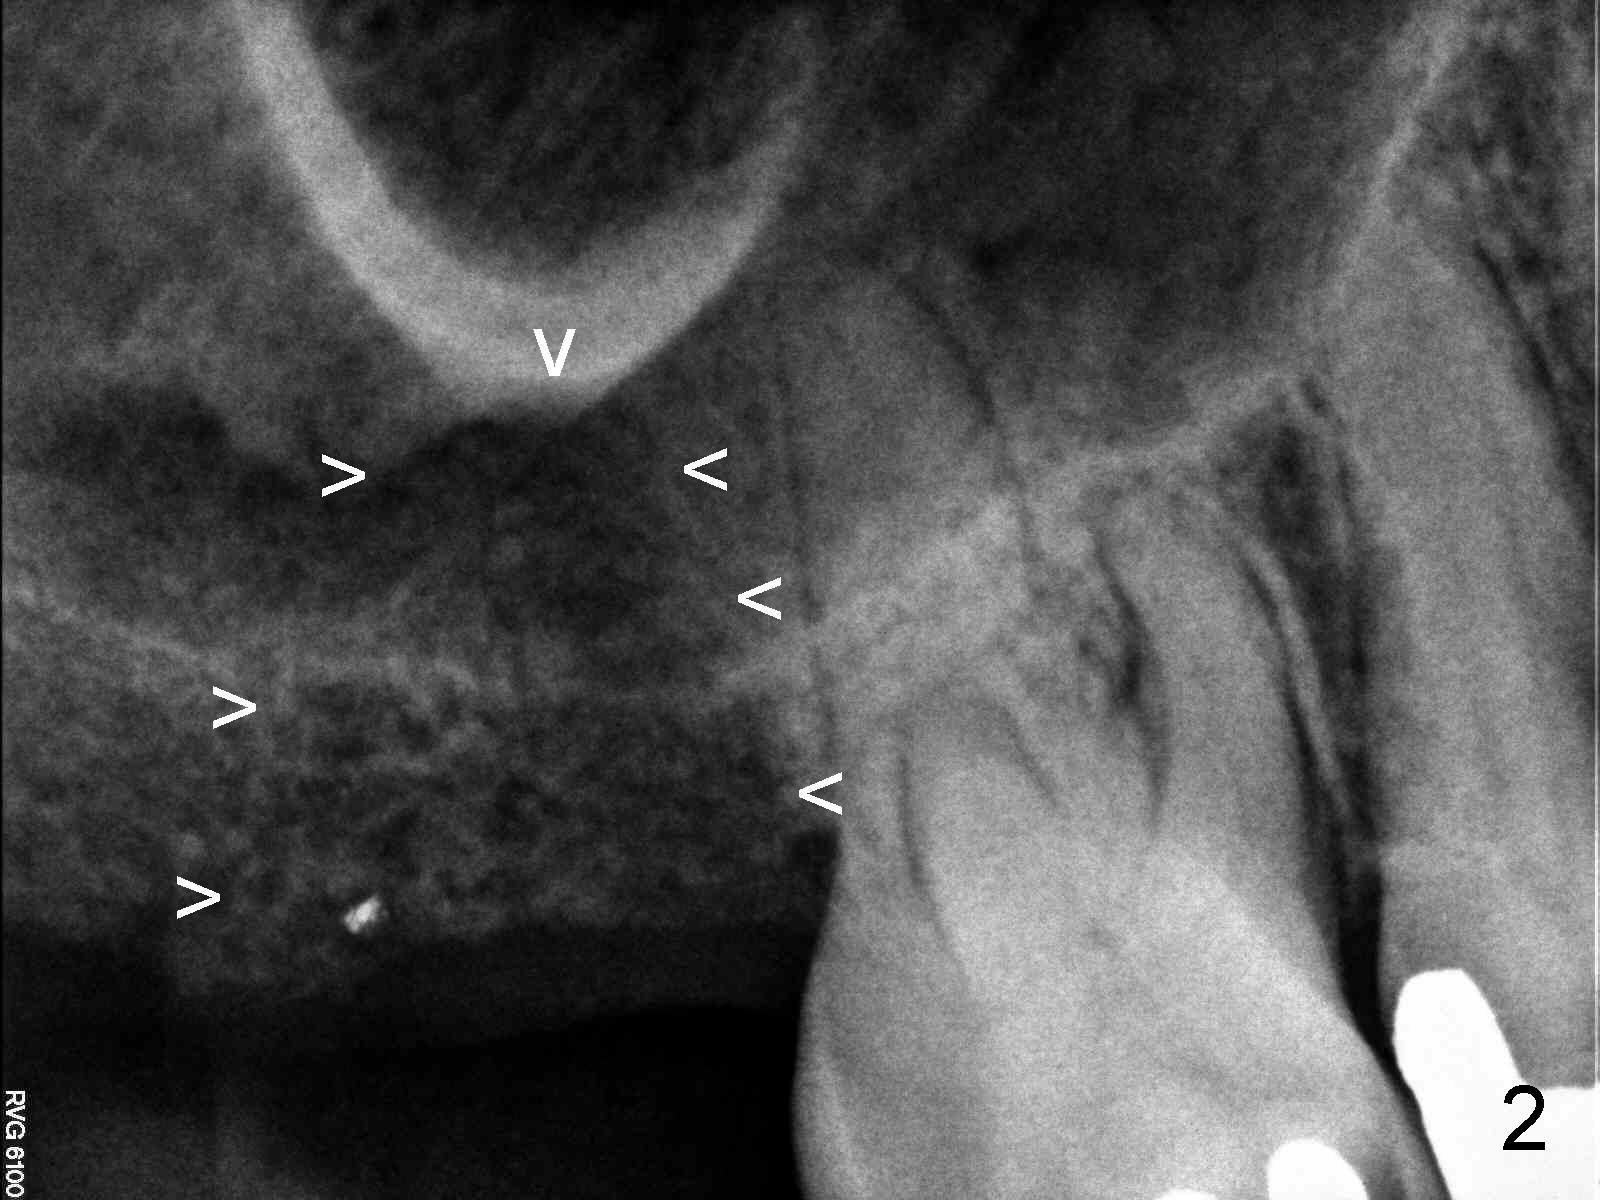

A 60-year-old man requests restoration of the missing upper right 2nd molar (Fig.1).  It appears that the bone height is limited (between white and red arrowheads, approximately 5 mm (Fig.5)).  Study of the sinus floor in association with the roots of the 1st molar reveals that the palatal root (P) appears inside the sinus.  In fact it is not.  Therefore there is bone apparently inside the sinus.

For the same reason, the root of the 2nd molar must have been above the sinus floor (Fig.2 arrowheads).  CBCT may confirm the fact.